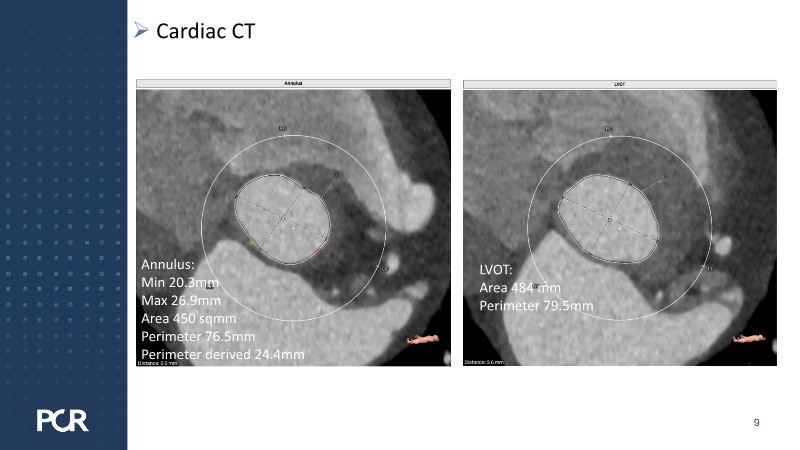

Discover how thoughtful index valve selection and implantation techniques can shape the long-term management of patients undergoing TAVI. This PCR London Valves 2025 session highlights treatment considerations for low- and intermediate-risk patients, explores how valve choice affects the feasibility of future interventions, and examines strategies to achieve optimal and durable clinical outcomes. Follow real patient case with imaging analysis, hemodynamic insights in small annuli, and discussions on planning for future revalving and coronary access.